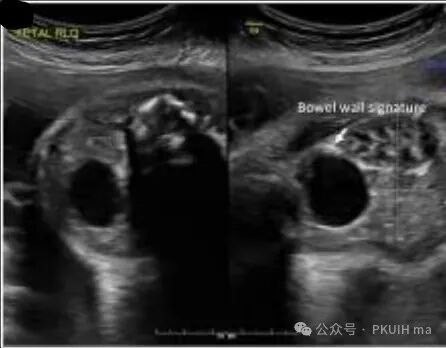

上图是一个孕24周的胎儿回肠重复囊肿病例的超声和MRI,在后期随访观察中囊肿由1.5cm(24周)长到2.4cm(37周)超声下显示囊肿边缘有肠壁特征(箭头所示)